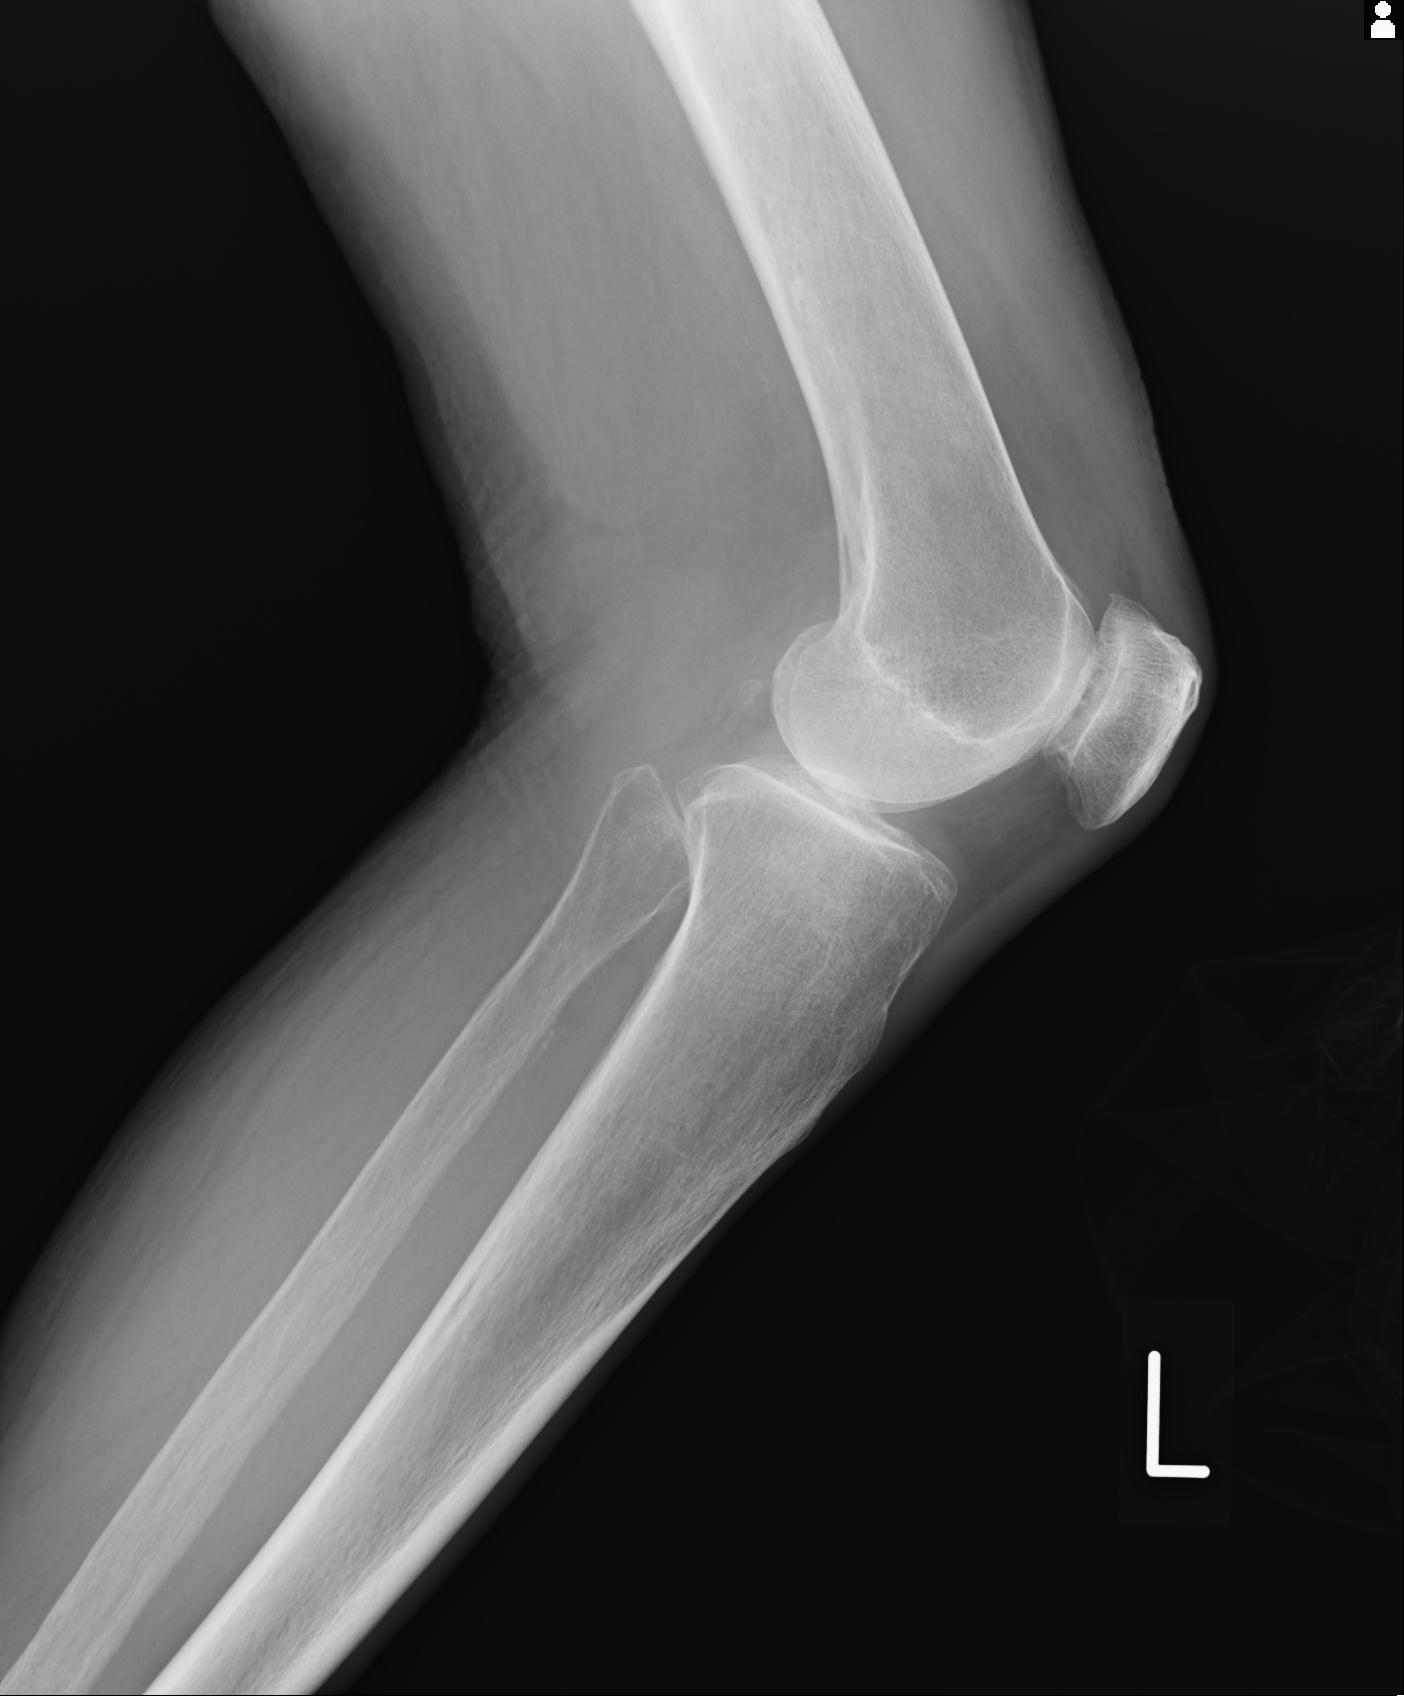

49554 3/13 膝 4R 3/16 4R 1/18 2R 78歳男性 膝蓋骨骨折